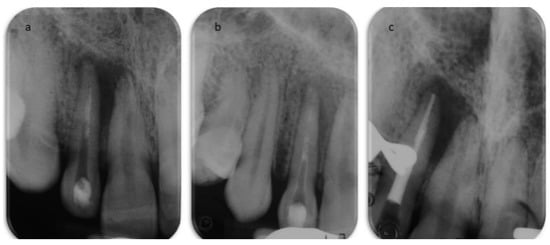

2. Case Report